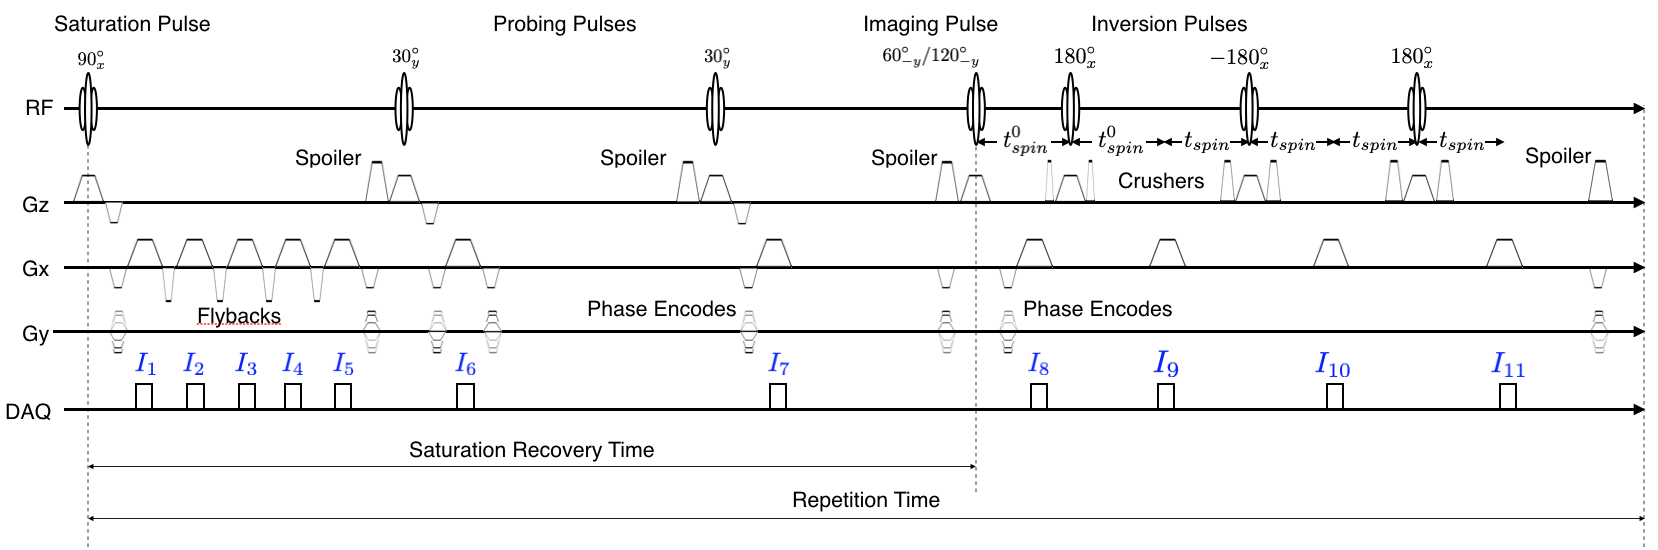

The complete multiMap sequence is shown in Fig. 1. A Cartesian spin-warp (2DFT) trajectory is used for acquisition. A repetition of the sequence consists of seven RF pulses (which are labeled with flip angles in Fig. 1, named the saturation pulse, the probing pulses, the imaging pulse, and the inversion pulses) and eleven acquisitions. The index of the image that corresponds to each acquisition is labeled in blue above the acquisition waveforms in Fig. 1. For each line of the trajectory, there are two repetitions (two segments): one for an imaging pulse with a flip angle of and another for an imaging pulse with a flip angle of .

The second inversion pulse is negated to account for inaccuracy in the flip angle; the crusher gradients of the second/third inversion pulses have double/quadruple the area of the crusher gradients of the first inversion pulse, respectively, to prevent any stimulated echoes from constructively interfering with each other. Since a spin-warp imaging trajectory was used for acquisition, all images are reconstructed with an inverse two-dimensional Discrete Fourier Transform. Algorithm 1 and its accompanying descriptions detail the procedure for estimating the quantitative maps from these reconstructions.

Figure 3 shows the axial slice images generated by the multiMap sequence. Figure 3 (a) and (b) show the magnitude and phase images, respectively. The top/bottom rows of each sub-image show the acquisitions of the first/second segments, respectively for a multiMap scan with a repetition time of ms and a saturation recovery time of ms. The total scan time for this image was minutes and seconds.